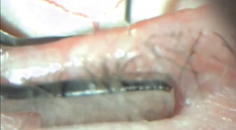

Simply by using basic tools already in your office, you can investigate the signs and symptoms of DED more thoroughly, which will help you to establish a dry eye practice quickly. Although patients’ subjective chief complaints are helpful, staining the cornea and assessing the meibomian gland function of every patient can also help you to understand the severity of their DED status. Spending a few extra minutes with patients to identify any evidence of DED and to educate them about their condition will benefit both them and your practice.

- Use basic tools such as sodium fluorescein staining to consistently look for signs and symptoms of DED in every patient.